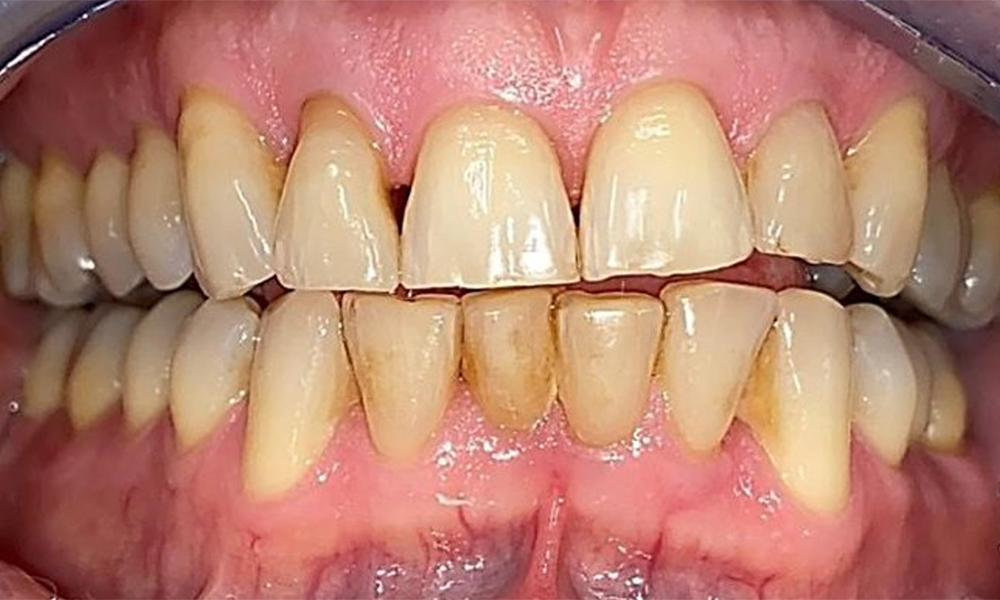

Left lateral view including the recessions.

Fig. 4 Left lateral view including the recessions. © Dr R. Krapf

The patient has a full dentition with 28 teeth, which includes amalgam and composite fillings in the molar and premolar regions. There is a visible clinical marginal gap present on tooth 14. Tooth 27 has an adequate gold inlay. There are also generalized attritions and abrasions. (Fig. 2, Fig. 3, Fig. 4, Fig. 5, Fig. 6)

Periodontal findings

The patient has stage II, grade B periodontitis (5). At 1 to 3 mm, the clinical probing depths were within the physiological range. Localized probing depths of 5 mm were observed on the mesiopalatal aspects on both 17 and 27. There are generalized recessions of 1–3 mm with partial loss of the interdental papillae (Fig. 2, Fig. 3, Fig. 4)